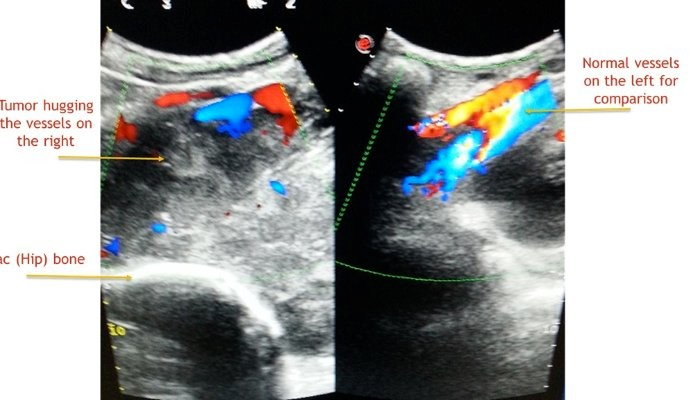

Till i spoke to him ,i thought he had a common easily curable illness.I learnt from him that ,in last 3 months he consulted 2 doctors,one of them a surgeon with no respite.One had treated him empirically and while  the other had referred him to a vascular surgeon,specialist dealing with blood vessels of legs .The vascular surgeon rightly requested a blood vessel study(Doppler ultrasound test)of the leg.I did a detailed examination of veins and arteries of the leg and found them normal.And  radiologists do not stop till they unearth the mystery of diagnosis.I gently interrogated his abdomen with ultrasound.I was not happy with what i found.It was a  dangerous tumour (sarcoma )involving muscles and deep structures of abdomen(retro peritoneum)impeding the fluid flow from leg and hence causing its swelling. Had the radiology scan been performed earlier,delay in diagnosis could have been avoided.

One cannot neglect leg swelling irrespective of the age.Appropriate diagnostic scanning should be carried out in consultation with radiologist.